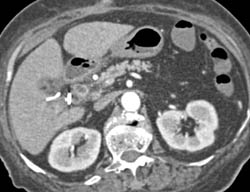

Cholangiocarcinoma of the Distal Common Bile Duct (CBD) Which Is Enhancing- See Full Sequence